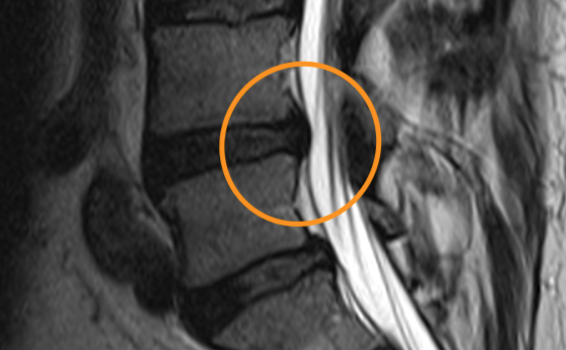

Hérnia Discal

Nas hérnias discais, a dor é secundária à doença dos discos (classificada na nomenclatura médica por “protrusões”, “procidências” ou “hérnias” discais), sobretudo nos segmentos lombar e cervical da coluna vertebral.

Os discos intervertebrais podem deformar-se saindo parcialmente comprimindo e/ou provocando inflamações nas raízes nervosas e, originar para além de dor na coluna, dor nos segmentos dependentes das estruturas nervosas, traduzidos por dor, dormência ou fraqueza muscular no braço ou na perna (vulgo dor “ciática”). Nos casos mais graves, uma hérnia do disco pode comprimir os nervos que controlam a bexiga e o intestino, resultando em incontinência urinária e perda de controlo do intestino.